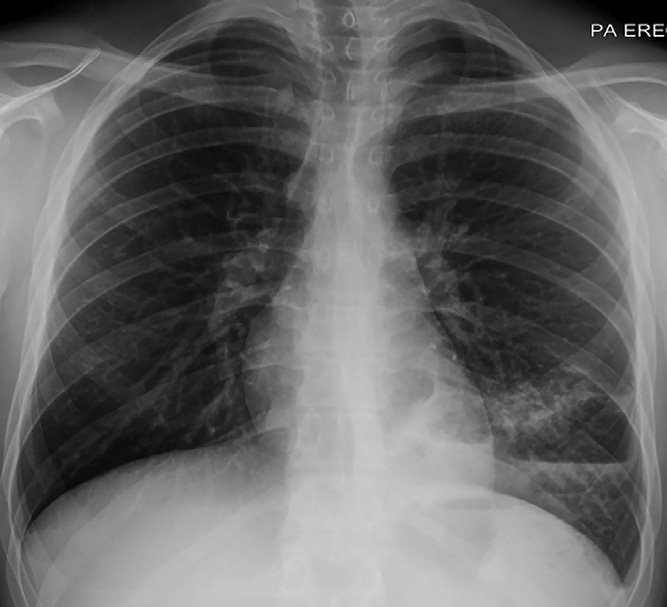

醫脈通編譯整理,未經授權請勿轉載。病例資料患者男,19歲,因干咳、發熱和全身不適2周于急診科就診。患者左側胸痛,否認咯血、體重減輕或盜汗病史。患者不吸煙,既往有哮喘和兒童期反復下呼吸道感染病史,其他病史無特殊。實驗室檢查顯示白細胞計數13.6×109/L↑(中性粒細胞79%;淋巴細胞12%),C反應蛋白96 mg/L↑。胸部X線檢查顯示左肺下葉實變伴氣液平面